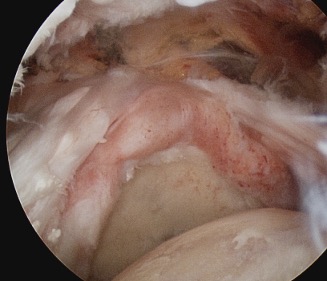

Arthroscopy

Tear patterns of supraspinatus and infraspinatus

| Crescent shaped | U shaped | L Shaped |

|---|---|---|

|

Small to medium tears Repair to footprint |

Large tears Need margin convergence then repair to footprint |

Antero-superior or postero-superior tears Need to mobilize cuff anterior or posterior |

|

|

|

Crescent, U shaped and massive rotator cuff tears